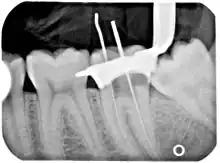

Another common complication of root canal therapy is when the entire length of the root canal is not completely cleaned out and filled (obturated) with root canal filling material (usually gutta percha). On the other hand, the root canal filling material may be extruded from the apex leading to other complications. The X-ray in the right margin shows two adjacent teeth that had received bad root canal therapy. The root canal filling material (3, 4, and 10) does not extend to the end of the tooth roots (5, 6 and 11). The dark circles at the bottom of the tooth roots (7 and 8) indicated infection in the surrounding bone. Recommended treatment is either to redo the root canal therapy or extract the tooth and place dental implants. Poor quality filling material or sealant may also cause root canal treatment to fail.[47]